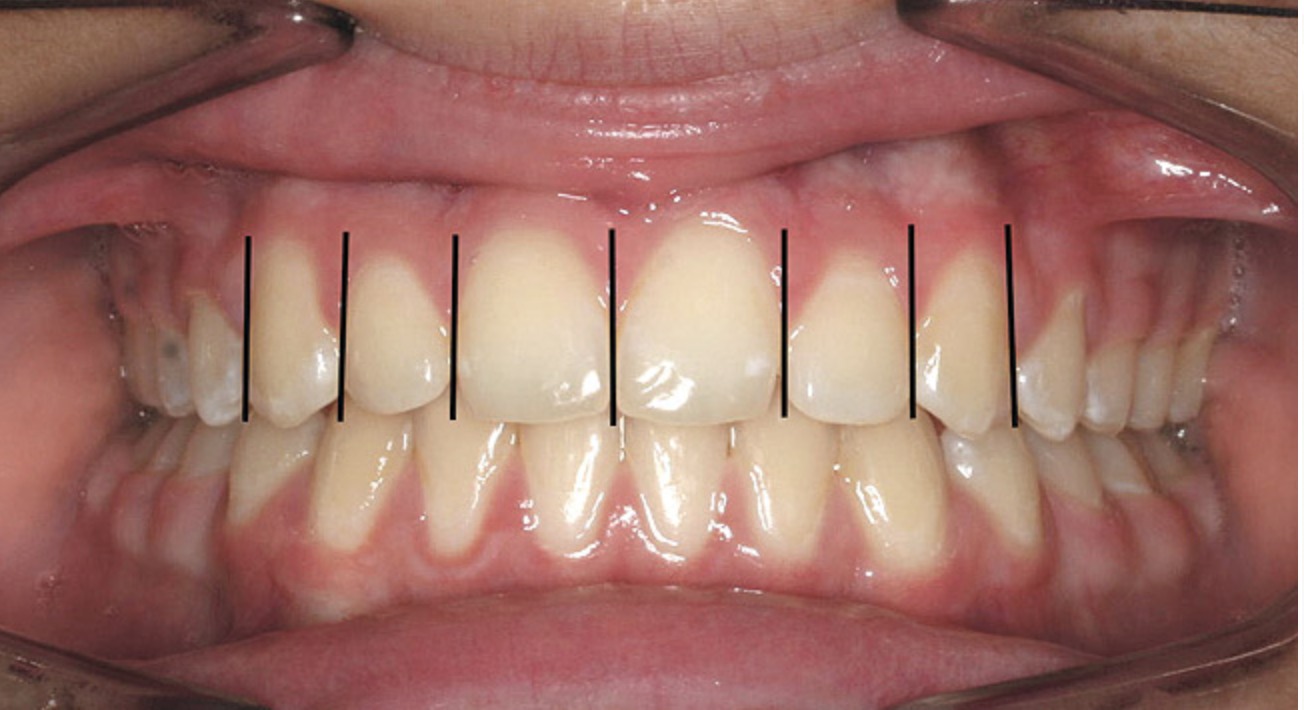

Figure 2   A balanced appearance of the anterior teeth is represented by a "golden proportional" of 1.618 for the maxillary central incisor, 1 for the lateral incisor, 0.618 for the canine.

Figure 2

The proportions of the teeth make a significant difference in the balance of the smile. Most restorative dentists are keenly aware of the importance of the golden proportion (Figure 2). When the maxillary lateral incisors are pegged or undersized, the orthodontist should be asked to redistribute the spaces. By positioning teeth properly, the restorative dentist can fabricate restorations to ideal proportions. When anterior teeth are crowded or broken down with loss of space, orthodontic alignment allows the natural proportions to be restored.